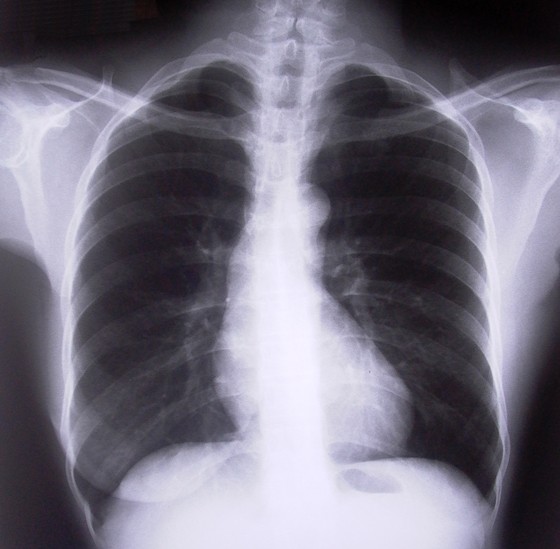

A vacina cubana para câncer de pulmão é barata e tem baixa toxicidade (Foto: Free Images)